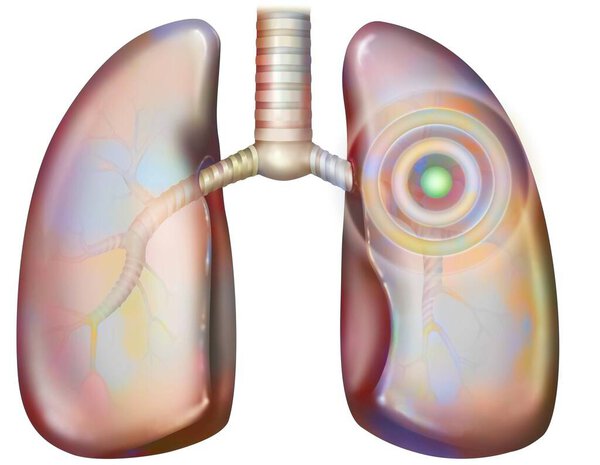

- Рак легких курильщика (с наличием депозитов смолы в бронхах).

Рак легких курильщика (с наличием депозитов смолы в бронхах).

Рак легких курильщика (с наличием депозитов смолы в бронхах).